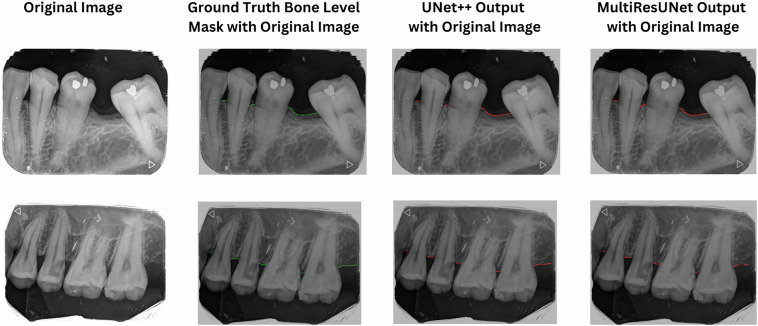

Dental diseases are one of the most common diseases that affect humans. Clinicians employ several techniques for diagnosing and monitoring dental diseases, with intra-oral periapical (IOPA) radiographs being among the most commonly utilized methods. The development of artificial intelligence (AI) technologies for analyzing oral radiographs is being explored across various imaging modalities. However, the limited availability of publicly accessible datasets has been a significant challenge. Although datasets of dental radiographs are available, most of these datasets contain panoramic radiographs with teeth segmentation only. This new data set includes IOPA radiographs with annotations of important landmarks along with tooth segmentation. The dataset includes 1000 images with marked landmarks, along with metadata. Researchers can leverage this resource to create AI solutions for analyzing IOPA radiographs.